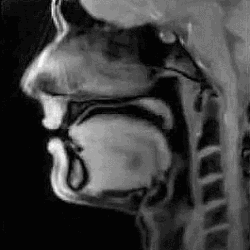

这是我们正在用舌头和声带发出声音说话